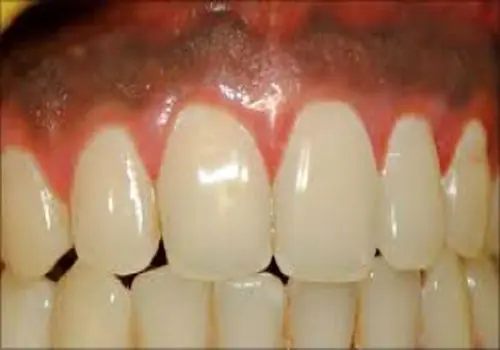

عفونت یا التهاب لثه یکی از شایعترین دلایل احساس درد در ناحیه لثه و فک پایین است. در این حالت، بافت لثه قرمز، متورم و گاهی همراه با خونریزی میشود. درد معمولا در اطراف دندانهای عقبی یا نزدیک محل التهاب احساس میشود و ممکن است هنگام جویدن یا فشار دادن فک تشدید گردد. بوی بد دهان و طعم ناخوشایند نیز از نشانههای عفونت لثه هستند.

درمان درد لثه و فک پایین ناشی از عفونت شامل جرمگیری حرفهای، استفاده از دهانشویه آنتیباکتریال و در صورت نیاز مصرف آنتیبیوتیک است. مراجعه به دندانپزشک برای کنترل عفونت در مراحل اولیه، از پیشرفت بیماری، آسیب به استخوان فک و بازگشت علت درد لثه و فک پایین جلوگیری میکند.